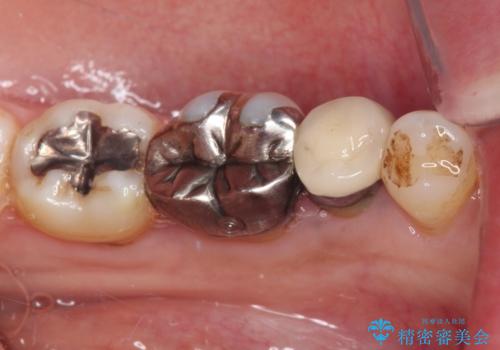

- 奥歯の銀歯をセラミックの白い歯にして、しみる症状も改善したいとのことで来院された患者様です。

知覚過敏の症状が強い歯と、銀歯の範囲や銀歯の下のむし歯が大きい歯は、インレー修復では対応が難しいためオールセラミッククラウンで、インレー修復で対応が可能な歯ではセラミックインレーにて修復することとしました。

知覚過敏の症状はなくなり、希望通りの白い歯になったと、患者様は大変満足されました。